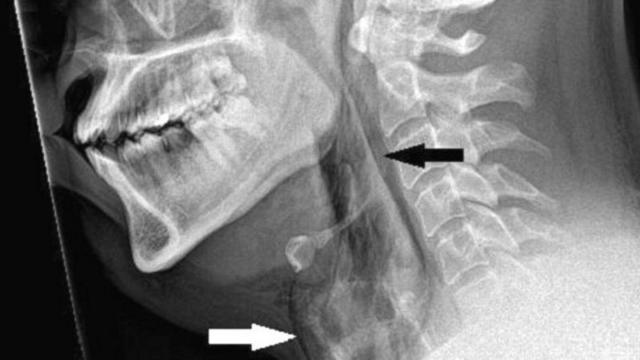

Paciente teve rupturablaze expert login2 mm na traqueia

Os exames revelaram que ele sofreu uma rupturablaze expert login2 mm na traqueia.

O caso foi documentado na revista médica BMJ Case Reports.

Um rompimento repentino na garganta, conhecido clinicamente como "ruptura traqueal espontânea", é raro e pode ser potencialmente fatal.

No novo caso relatado, médicos examinaram o paciente e ouviram um estalo ao tocar seu pescoço.